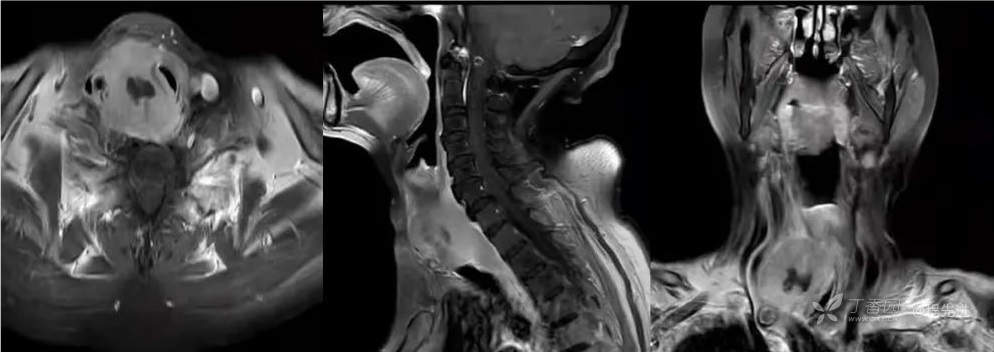

MR

增强